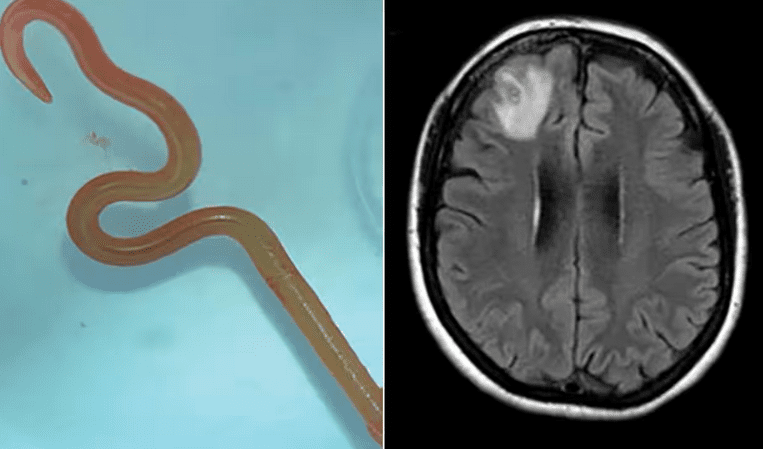

Ζωντανό σκουλήκι αφαιρέθηκε χειρουργικά από τον εγκέφαλο γυναίκας

Ένα ζωντανό σκουλήκι, μήκους οκτώ εκατοστών, αφαιρέθηκε χειρουργικά ζωντανό από τον εγκέφαλο μιας 64χρονης γυναίκας στην Αυστραλία.

Όπως γράφει η Australian Guardian, η 64χρονη είχε παραπονεθεί για πόνους στο κεφάλι και προβλήματα μνήμης. Ανέλαβαν οι νευροχειρουργοί σε νοσοκομείο της Καμπέρα για να την εξετάσουν. Αρχικά υπέθεσαν ότι η αιτία ήταν ένας «τραυματισμός». Κατά τη διάρκεια της επέμβασης, ωστόσο, βρήκαν και αφαίρεσαν ένα ζωντανό σκουλήκι. Το παράσιτο ήταν Ophidascaris robertsi, το οποίο συνήθως απαντάται μόνο σε πύθωνες, σύμφωνα με μελέτη που δημοσιεύεται στο περιοδικό Emerging Infectius Diseases.

. Στη συνέχεια η γυναίκα μεταφέρθηκε στο νοσοκομείο της Καμπέρα. Μια μαγνητική τομογραφία του εγκεφάλου της αποκάλυψε τελικά ανωμαλίες που απαιτούσαν χειρουργική επέμβαση.

«Αλλά οι νευροχειρουργοί σίγουρα ποτέ δεν πίστευαν ότι θα έβρισκαν ένα σκουλήκι που στροβιλίζεται», ανέφερε ο καθηγητής Σαντζάγια Σεναναγιάκε, ειδικός στις μολυσματικές ασθένειες στο νοσοκομείο της Καμπέρα ο Σεναγιάκε στον Guardian. «Οι νευροχειρουργοί ασχολούνται τακτικά με λοιμώξεις στον εγκέφαλο, αλλά αυτό ήταν ένα εύρημα που κανείς δεν το περίμενε».

«Αυτή είναι η πρώτη περίπτωση εμφάνισης Ophidascaris robertsi σε άνθρωπο, οπουδήποτε στον κόσμο», ανέφερε ο καθηγητής Σαντζάγια Σεναναγιάκε. «Από όσο γνωρίζουμε, αυτή είναι επίσης η πρώτη περίπτωση που επηρεάζεται ο εγκέφαλος ενός είδους θηλαστικού, ανθρώπινου ή μη».